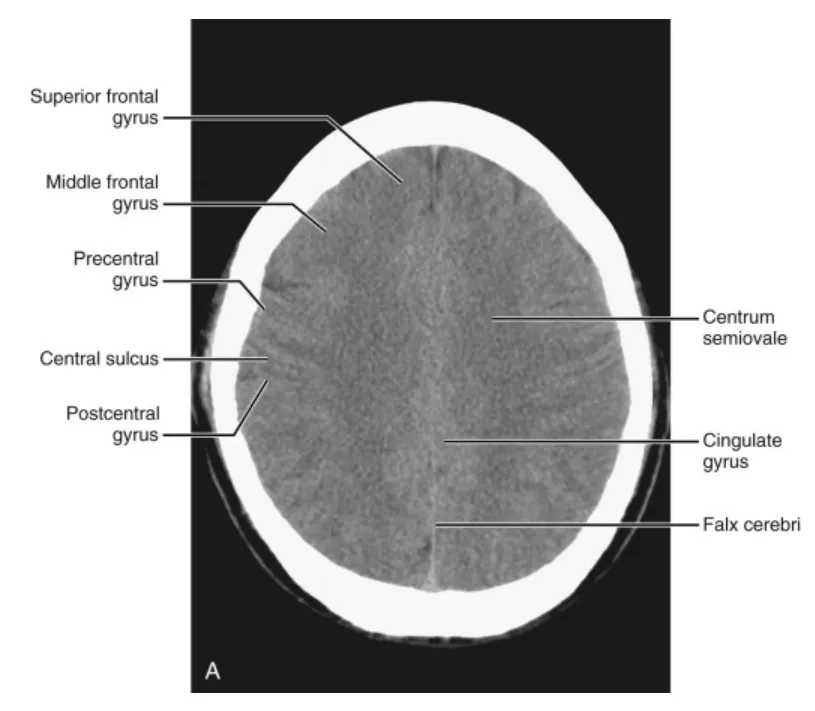

(해설) Brain CT의 각 Level 별로 보이는 구조물입니다.

(4) Above the ventricular level

이 단면은 주로 frontal lobe, parietal lobe, 그리고 occipital lobe의 일부를 포함합니다. superior frontal sulcus는 superior frontal gyrus를 middle frontal gyrus와 분리하며, interhemispheric fissure와 평행하게 잘 묘사됩니다. precentral, central, postcentral sulci를 포함한 세 개의 평행한 sulci가 이 수준에서 잘 시각화됩니다. central sulcus는 스캔의 중간 부분에서 확인할 수 있습니다. precentral과 postcentral sulci는 motor와 sensory cortices의 윤곽을 그립니다. interhemispheric fissure는 전체 길이에 걸쳐 볼 수 있으며, 그 사이에 falx가 있습니다. interhemispheric fissure의 측면으로 거대한 white matter인 centrum semiovale이 잘 나타납니다.